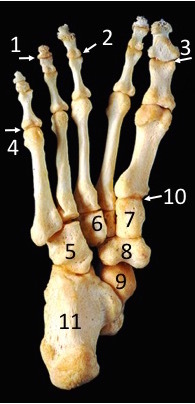

Which muscle flexes joint 3?

Flexor hallucis longus

Muscles 2, 3 and 4 comprise which muscle layer of the sole of the foot?

2nd layer

Which muscle inserts on region 5?

Fibularis brevis